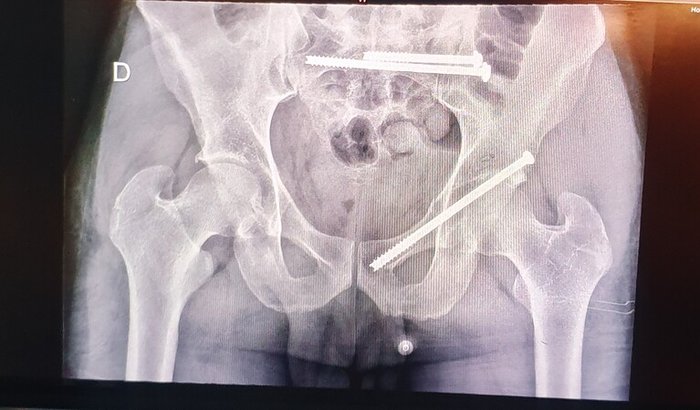

Fraturei a pelvis e o sacro ao cair do telhado(5m de altura).

10cm mais pra cima e nunca mais andava.